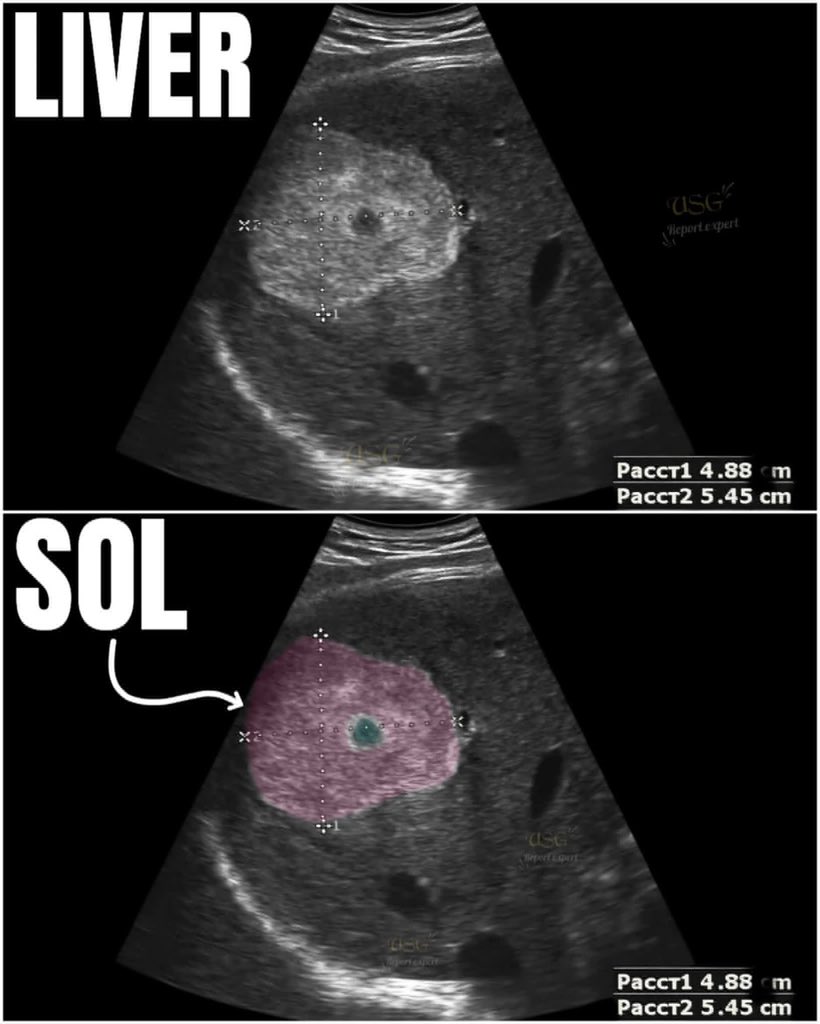

🧐 “Can you identify which liver segment 😳 this SOL is located in?” #fblifestyle #ultrasound #ultrasoundtech #ultrasoundlife #ultrasoundtechnologist #LiverDisease #liverhealth #liverdetox

EchoTech_4's tweet image. 🧐 “Can you identify which liver segment 😳 this SOL is located in?”